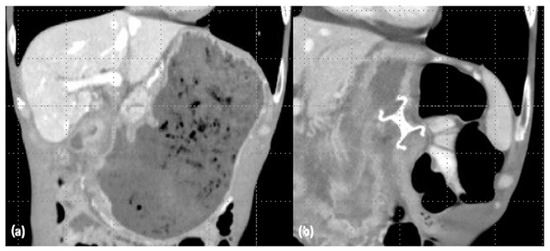

4. EUS-Guided Gastroenteric-Anastomosis

6. EUS-GE Outcomes and Comparison to Other Techniques